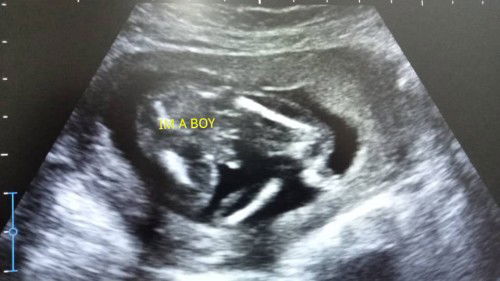

Excited to become a mum

17week pregnant

17 week dah nampak gender. Excited sikit sbb first baby.#firstmom #firstbaby